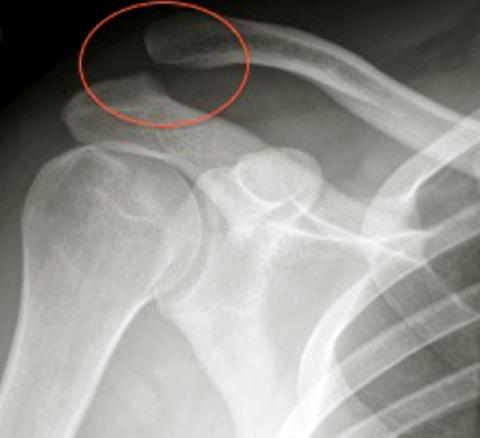

Disjonction acromio-claviculaire

2. Disjonction acromio-claviculaire